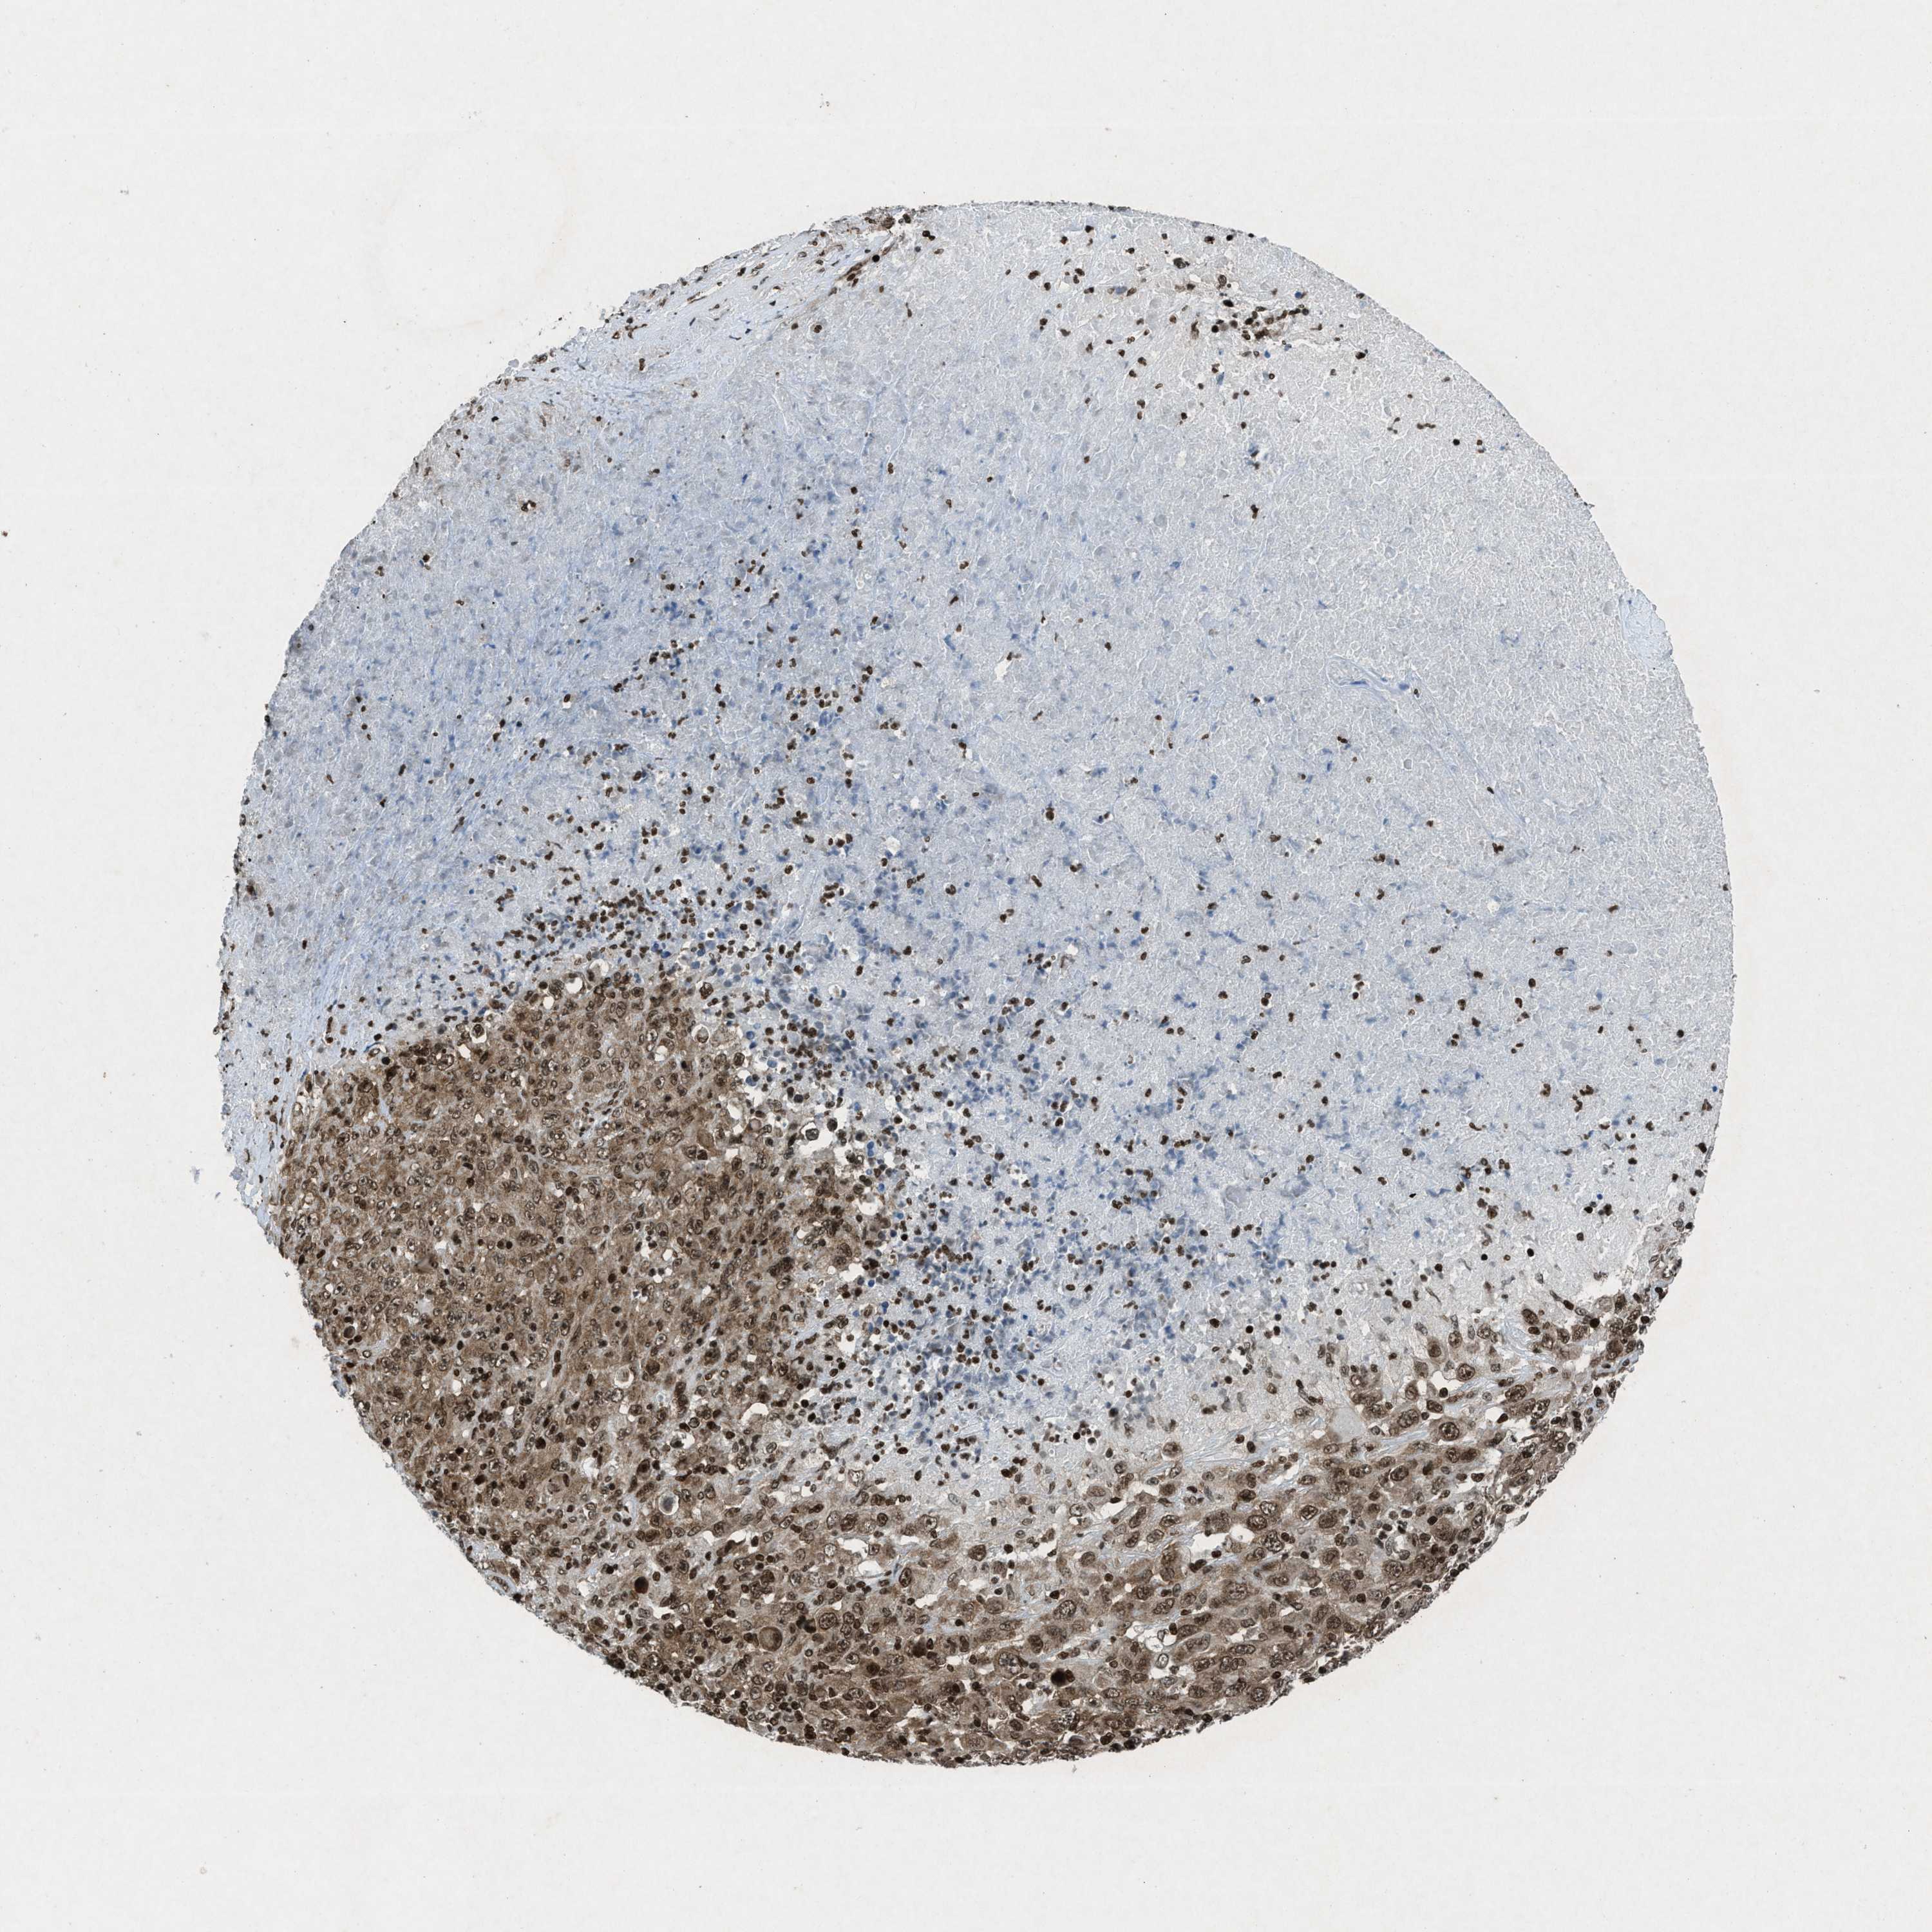

MELANOMA - Protein expressioni

A mouse-over function shows sample information and annotation data. Click on an image to view it in a full screen mode. Samples can be filtered based on level of antibody staining by selecting one or several of the following categories: high, medium, low and not detected. The assay and annotation is described here.

Note that samples used for immunohistochemistry by the Human Protein Atlas do not correspond to samples in the TCGA dataset.

Antibody stainingi

Antibody staining in the annotated cell types in the current human tissue is reported as not detected, low, medium, or high, based on conventional immunohistochemistry profiling in selected tissues. This score is based on the combination of the staining intensity and fraction of stained cells.

Each image is clickable and will lead to virtual microscopy that enables deeper exploration of all samples and also displays staining intensity scores, fraction scores and subcellular localization as well as patient and tissue information for each sample.

Antibody HPA061593

Antibody CAB016327

Staining

High

Medium

Low

Not detected

Intensity

Strong

Moderate

Weak

Negative

Quantity

>75%

75%-25%

<25%

None

Location

Nuclear

Cytoplasmic/membranous

Cytoplasmic/membranous,nuclear

Malignant melanoma, NOS

Malignant melanoma, Metastatic site